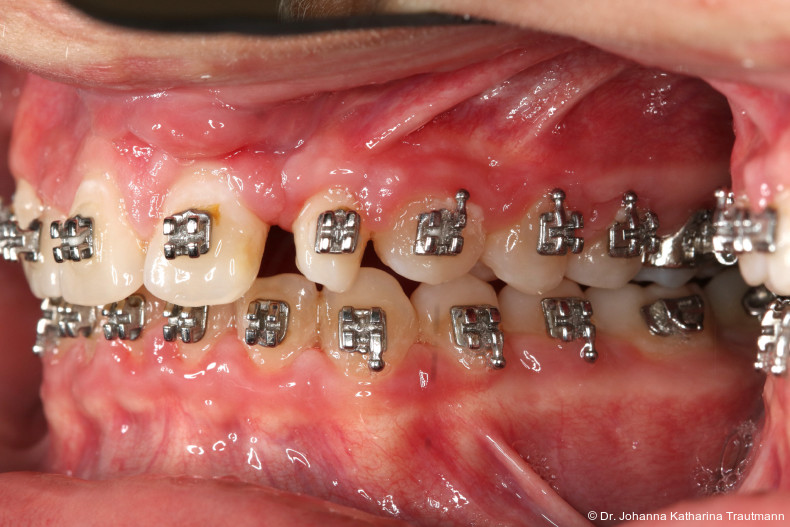

Im Rahmen der Multibrackettherapie wurde bewusst der Zahn 13 aus dem Hauptnivellie rungsbogen ausgelassen, um Kippungen und Asymmetrien im Zahnbogen zu vermeiden. Der Zahn 23 wurde locker mit einer Distanz ligatur angebunden, um eine weitere Bewegung nach vestibulär zu erreichen. Auf einem 0.019" x 0.025" Stahlbogen erfolgte anschlie ßend mittels Umgehungsbiegung sowie eines Overlaybogens (0.014" NiTi) die Integration des Zahnes 13 in den Zahnbogen. Die Zwischendiagnostik nach einem Jahr festsitzender Behandlung zeigte eine gelungene Bisshebung bei guter Nivellierung des Okklusionsplanums und orthoaxialer Einstellung der Frontzähne. Die Zahnbögen präsentierten sich harmonisch ausgeformt, es zeigte sich jedoch eine verbleibende Torqueproblematik an bei den Oberkiefereckzähnen. Nach Freilegung und Einstellung verlagerter Eckzähne ist eine korrekte Torque und Angulationssteuerung häufig eine Herausforderung. Während vestibulär verlagerte Zähne zu gingivalen Rezessionen neigen, behalten palatinal verlagerte Zähne oft ihre palatinale Wurzelstellung bei.13, 14 Die genutzte MBTPrescription der Brackets bietet die Möglichkeit, zwischen +7°, 0° und –7° Torque zu wählen.15 In einem 0.022" System ist bei Verwendung eines 0.019" x 0.025" Bogens jedoch mit einem Torqueverlust von etwa 10° zu rechnen.16

Eine rein klassische „Hochnivellierung“ führt daher zu keiner aus reichenden Torqueübertragung. Alternativ kann ein individualisiert eingebogener Einzelzahntorque eingesetzt werden, um diesen Verlust auszugleichen. Zum Zeitpunkt der Zwischendiagnostik bestand weiterhin eine asymmetrische Bisslage sowie ein vergrößerter Overjet, die beide im weiteren Verlauf mithilfe intermaxillärer Gummizüge korrigiert wurden. Bereits in dieser Phase erfolgte eine Rück sprache mit der Abteilung für Präventive Zahnmedizin, Parodontologie und Kariologie, um eine optimale Ausgangssituation für den späteren odontoplastischen Umbau des Zahnes 22 zu schaffen. Eine präzise kieferorthopädische Einstellung kann die restaurative In vasivität deutlich reduzieren und die Gewebe symmetrie, einschließlich Papillen und Gin giva verlauf, positiv beeinflussen.17, 18 Optimalerweise werden Funktion und Ästhetik vor Entfernung der Multibracketapparatur interdisziplinär abgestimmt, um sowohl aus kieferorthopädischer als auch konservierender Sicht das bestmögliche Ergebnis zu erzielen. Auch das Terminmanagement sollte frühzeitig abgestimmt werden, um eine zügige Rehabilitation zu gewährleisten.

Längere Retentionszeiten ohne odontoplastischen Umbau können das Risiko eines Rezidivs des Zahnes 22 erhöhen. Dennoch ist häufig eine Abheilphase nach der Multibrackettherapie erforderlich, da sich gingivale Entzündungen oft erst nach ein bis drei Monaten vollständig zurückbilden.19–21 Um diesen Zeitraum zu überbrücken wurde an 22 die Kunststoffbasis der DVP (Doppel vorschubplatte) zur Retention sowohl mesial als auch distal extendiert. Schließlich wurden die Zähne 11, 21 und 22 kompositrestaurativ angeglichen, wodurch ein sehr gutes ästhetisches Ergebnis erzielt wer den konnte. Aufbauten mit Komposit bieten eine gute Möglichkeit, bei maximaler Schonung der Zahnhartsubstanz hypoplastische Zähne langfristig zu versorgen, und zeigten in ZehnJahresFollowups hohe Überlebensraten. Entscheidend ist hierbei eine ausgeglichene okklusale Lastverteilung, die mit hilfe einer physiologischen Frontzahnabstützung und gesicherten Okklusion durch die kieferorthopädische Vorbehandlung erreicht werden kann.22

Positiv hervorzuheben ist hingegen der er zielte Knochen erhalt beziehungsweise der partielle Attachmentgewinn im Bereich der Spalte. Wie sich in den Verlaufskontrollen der OPGAufnahmen erkennen lässt, führte die Bewegung der Zähne 21 und 22 in den Spaltbereich zu einer deutlichen Verbesse rung der knöchernen Situation. Obwohl das Knochenniveau nicht vollständig physiologisch ist, konnte ohne zusätzliche Knochenaugmentation eine stabile Knochen und Gewebesituation erreicht werden. Dass ein Attachmentgewinn durch gezielte kieferorthopädische Zahnbewegung möglich ist, wurde bereits von Melsen et al.22 beschrieben. Während sich die meisten nachfolgenden Studien auf parodontal vorgeschädigte Gebisse konzentrierten, zeigt der vorliegende Fall eine mögliche Übertragbarkeit dieser Mechanismen auf Spaltpatienten mit moderatem Knochendefizit.